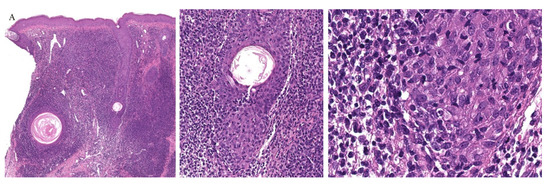

Clinically, the involvement of the hair follicle in GVHD can result in a variety of manifestations including non-scarring and scarring alopecias, a follicular rash, and comedonal lesions, among others [11]. Histologically, follicular variants have been described in both acute and chronic forms of GVHD (Figure 2) [12]. Unfortunately, the reported cases of acute follicular GVHD carried a high mortality rate while chronic follicular GVHD seems to confer a more favorable prognosis [13,14]. This involvement of the follicular epithelium has been attributed to inflammation around the bulge region of the hair follicle, likely due to the presence of stem cells in this area [15].

Eccrine gland involvement is also seen in GVHD. In addition to the classical histologic features, a lymphoplasmacytic infiltrate around the eccrine coils is a specific feature of GVHD (Figure 2) [16]. Eccrine squamous syringometaplasia has also been described in biopsy specimens of a patient with cutaneous and hepatic GVHD [17].

Figure 2. (AC) Graft versus host disease with perieccrine inflammation.